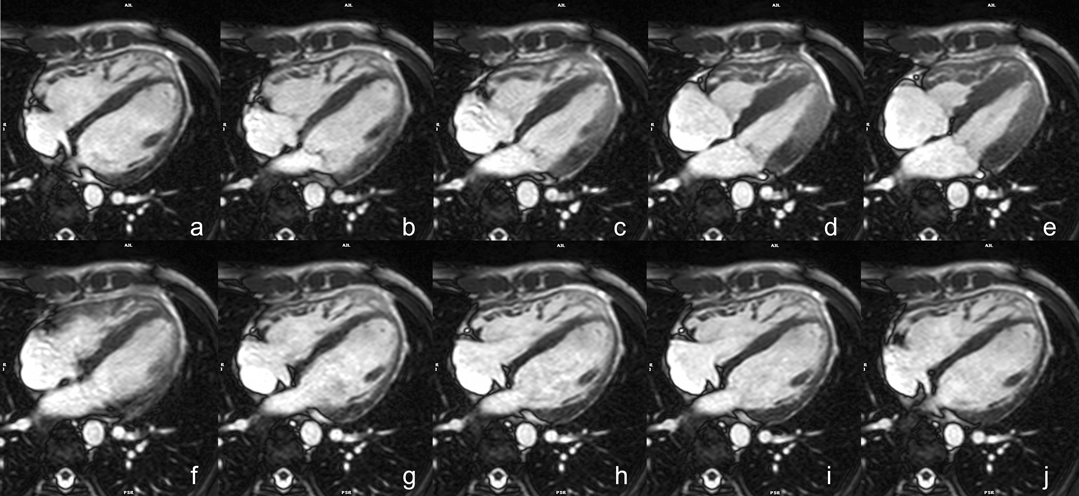

シネMRIの撮影

シネMRIは一心拍当たり数十コマの画像で心拍動を描出する(Fig. 1).この画像を連続的に再生(動画となる)することで,エコーのB modeと同様の映像を見ることができる(Movie 1).この画像を用いて心室の壁運動や心筋容積の評価を行うため,基本となる撮影法である.もちろん,心臓外の血管についても同様に評価可能で,体内で任意の断面を設定・評価できることが特徴的である.

Fig. 1 Cine image in 4-chamber view: Visible ventricular contraction

4. bSSFP長軸像シネMRI(Fig. 5

• 左室短軸断面以外に以下の基本3断面の撮影をする.検査時間の関係で,心臓全体をカバーするような撮影は行わず,撮影範囲は該当する3断面のみとすることが一般的である.

1. 四腔長軸像:二腔長軸像上で,僧房弁の中心,三尖弁の中心および心尖を通る断面.

2. 左室二腔像:すでに得られた垂直長軸断面から左室前壁・下壁を通るように設定.

3. 左室三腔像:心尖と僧房弁の中央を通り,左室流出路(LVOT)の中心と大動脈弁を含む断面.